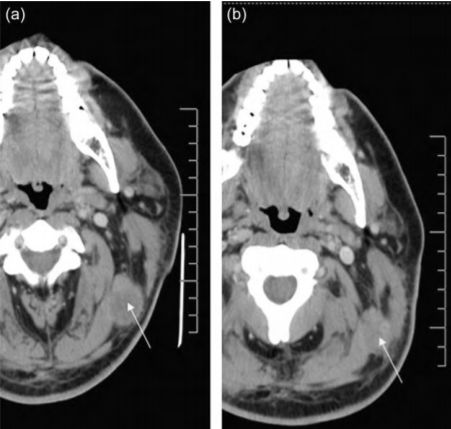

2008Ä꣬ÃÀ¹úÀ­Ê²´óѧҽѧÖÐÐĵÄÑо¿ÈËÔ±½«ÍâÔ´À©ÔöµÄNKÒìÌåϸ°û×¢Èëµ½ºÚÉ«ËØÁö»¼ÕßÌåÄÚ£¬½á¹û·¢ÏÖ£¬×¢Èë×¢ÈëNKϸ°ûºó£¬¸Ã»¼Õß×óÉϾ±²¿Ö×ÁöµÄÌå»ýÃ÷ÏÔ½µµÍ£¨´Ó3.15 cm¡Á2.54 cm¼õСÖÁ2.46 cm¡Á 1.76 cm£©¡£Í¬Ê±£¬¸ÃÑо¿Ò²ÎªÍâÔ´À©ÔöµÄNKÒìÌåϸ°ûÊÇ·ñ¿ÉÒÔ´ó¹æÄ£Ó¦ÓÃÓÚÖÎÁƺÚÉ«ËØÁöÌṩÁËÒ»¶¨µÄÀíÂÛÒÀ¾Ý¡£

NKϸ°ûÖÎÁÆÇ°ºó¶Ô±Èͼ